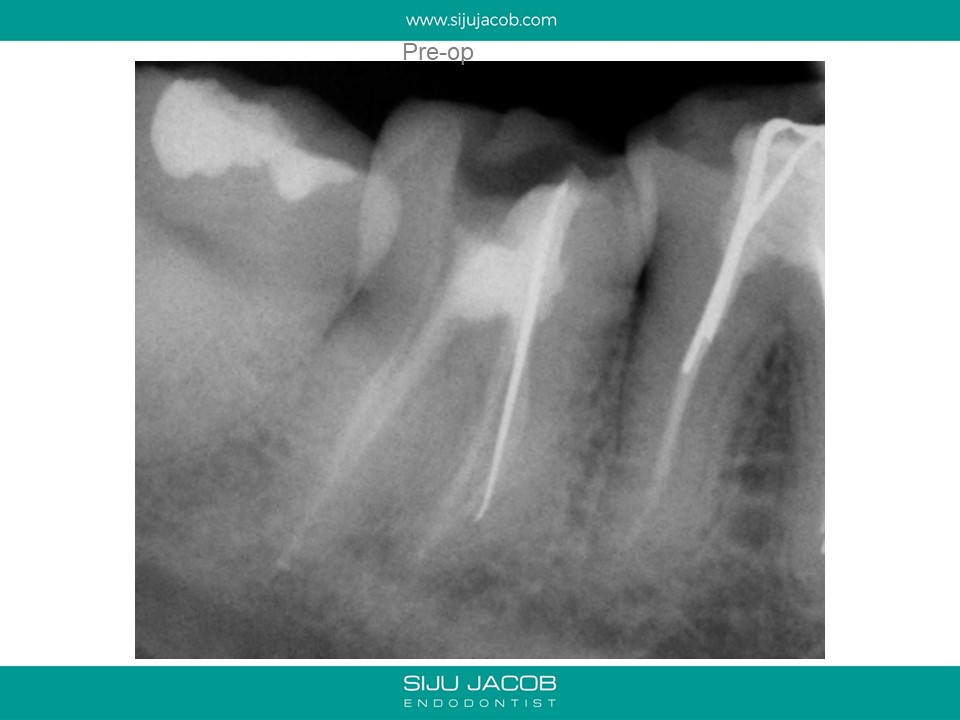

This was an old case i discovered on my comp. I treated this case in 2006. It is probably a good case to demonstrate the location of the middle mesial canal.

Strangely, the first thing that I thought when I saw this case today was, “Did this really benefit the patient? There wasn’t any lesion and the patient didn’t have any pain. Did my over-enlarging the canals through re-treatment actually weaken the tooth and therefore the long-term prognosis? I probably would have thought twice about re-treating this today.